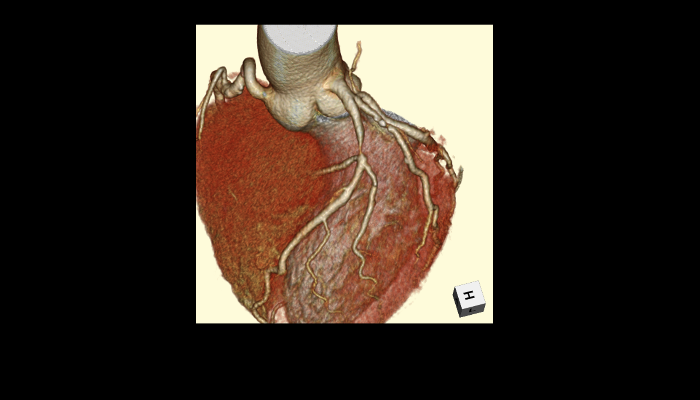

頭部CT画像 頭部CT脳出血や脳挫傷などの評価を行います。 胸部CT画像 胸部CT肺がんや肺炎や大動脈など胸部臓器を評価します。 心臓CT画像 心臓CT冠動脈を評価し、狭心症や心筋梗塞のリスクを検索します。 腹部CT画像 腹部CT肝臓・胆のう・膵臓・腎臓など腹部の重要臓器を評価します。 骨・関節CT画像 関節・骨CT骨折の評価に優れます。 動静脈CT画像 動脈・静脈CT動脈瘤や閉塞性動脈硬化症、深部静脈血栓症など血管の評価を行います。 大腸CT 大腸CT仮想内視鏡と言われる大腸の3D画像を得ることで苦痛の少ない大腸検査をすることができます。検査前日より検査食と下剤を服用していただきます。

心臓CT:Coronary CT

心臓を撮影し、冠動脈画像を描出する検査です。検査時間はおよそ30分です。

心臓CT画像